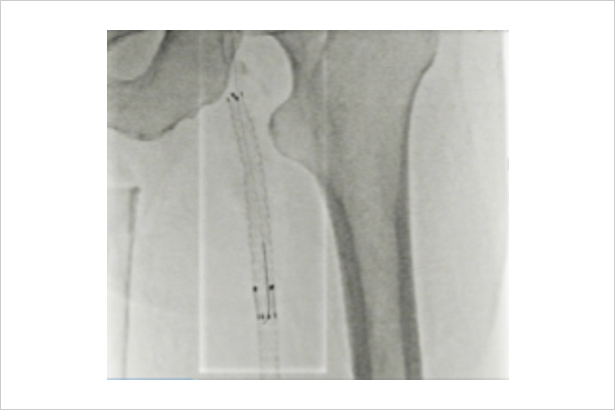

感興趣區域內顯示實時透視圖像,感興趣區之外無射線的靜止圖像作為背景,既保證了全局觀,又降低了輻射劑量